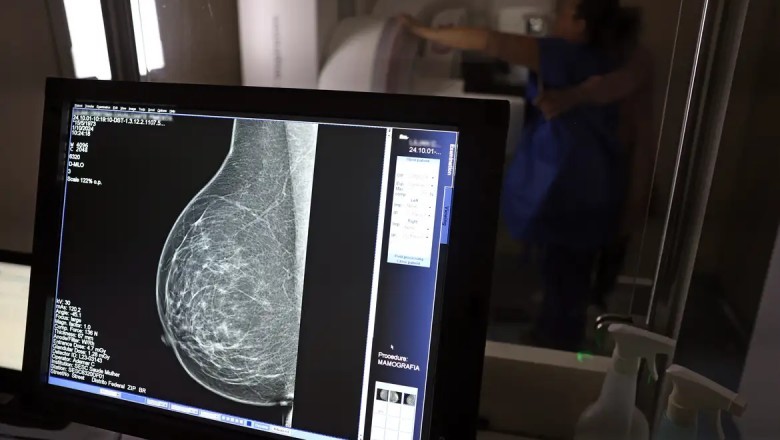

Segundo o CBR, os dados reforçam a necessidade de ampliar o rastreamento da doença por meio da mamografia também para mulheres com menos de 50 anos e acima dos 70 anos. Atualmente, a recomendação do Sistema Único de Saúde (SUS) contempla apenas mulheres entre 50 e 69 anos.

Entre janeiro de 2018 e dezembro de 2023, o país registrou 319.378 diagnósticos de câncer de mama. Do total, 157.439 ocorreram na faixa etária atualmente recomendada para rastreamento (50 a 69 anos). Já entre mulheres de 40 a 49 anos, foram contabilizados 71.204 casos. Outras 19.576 mulheres, com idade entre 35 e 39 anos, também receberam o diagnóstico, totalizando 33% dos casos fora do público prioritário.

O levantamento mostra ainda um aumento de 59% no total de diagnósticos da doença em seis anos. Em 2018, foram registrados 40.953 casos; em 2023, o número subiu para 65.283.